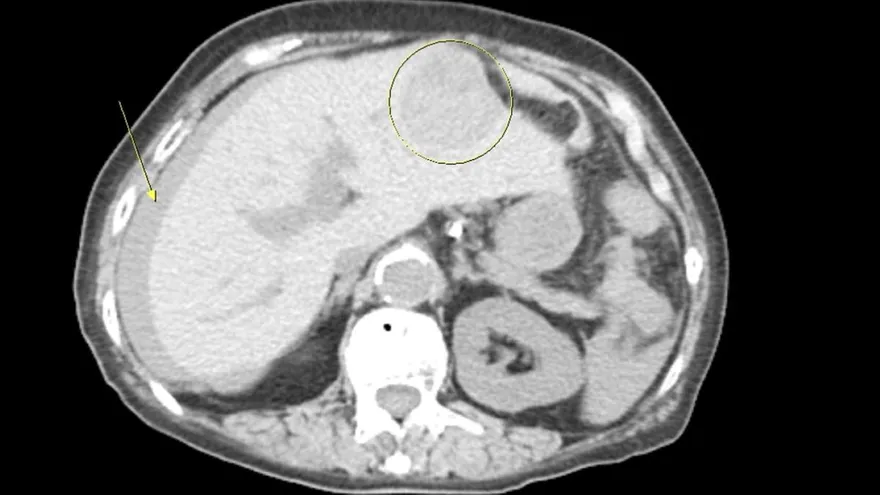

肝癌

肝癌自發性消失

免疫攻擊機制

腫瘤缺血缺氧

致癌物質的戒除

黃軒醫師